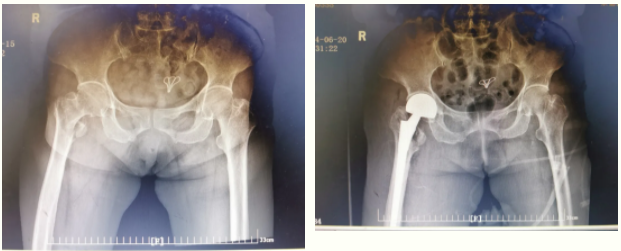

案例二:人工关节置换术

景德镇市第一人民医院骨科

大力发展亚专业学科

6月15日,90岁老人跌倒

紧急入市一院骨科就诊

急诊摄片示右侧股骨粗隆间骨折

骨科主任袁志峰及其团队

联合多学科专家

秉承ERAS快速康复理念

行人工关节置换术

患者可尽早下地走路

避免长期卧床带来的并发症

术后第一天

老人即可下地进行康复训练

六周后

可正常行走,康复出院

技术分享:关节置换是使用由聚乙烯、陶瓷、金属等材质制作的人工关节植入人体中,替换已失去功能的骨关节,提高肢体活动功能。关节置换出现率比较高的部位有髋关节、膝关节等。关节置换是一种比较先进且成熟的修复手术,能够比较好的改善关节损伤带来疼痛、活动障碍等不适现象,对提高患者的生活质量有比较积极的意义。